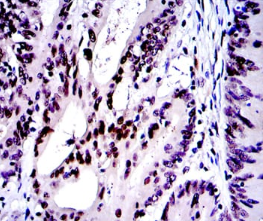

c-Jun Mouse Monoclonal antibody[4H9G9]

IHC    1/200 - 1/1000